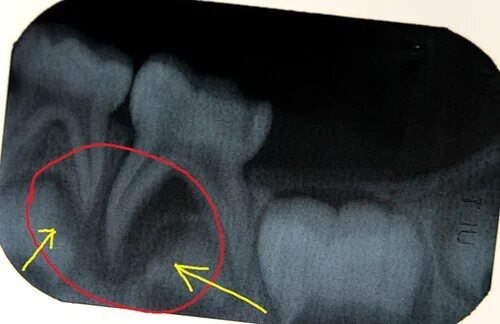

У ребенка нет зачатка постоянного зуба